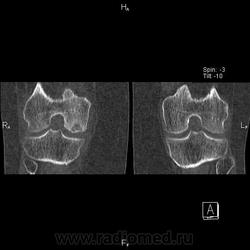

Здравствуйте! Давненько ничего не выкладывал. Нужна помощь. Женщина 1937 г.р. Жалобы на боли в правом коленном суставе уже давно. Долго ставили деф артроз.

Думаю что здесь частичный аваскулярный некроз медиального мыщелка бедренной кости. Ну а теперь вопросы:

3. Где выпот на КТ? Вижу в полости сустава и между мышцами по задней поверхности на уровне подколенной ямки( что это за сумка?). Забыл сделать реконструкцию с кернелем для мягких тканей, поэтому мягкие ткани такие пёстрые вышли, но выпот видно.

Да, но здесь часть эпифиза рассосалась, осталась только частично разрушенная субхондральная пластинка. Вот и думаю что это за стадия